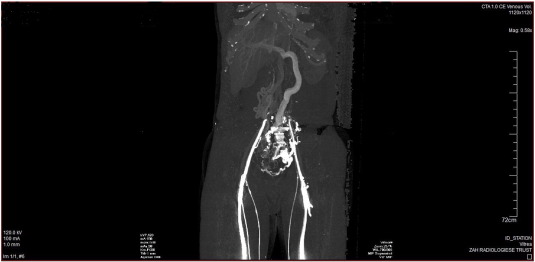

Fig. 1 ;  Fig. 2 are the CT angiography images of the venous system of the lower extremities and inferior vena cava of a 44 year old Caucasian male who presented with a long history of intermittent edema of both lower extremities. His clinical examination was perfectly normal. CT angiography of the lower extremities and IVC demonstrated patent popliteal, femoral and iliac veins with a completely absent IVC. Massively dilated collateral vessels were visible with large, dilated azygos and hemi-azygos veins. The azygos vein drained into the superior vena cava. In addition the lumbar veins were dilated with multiple collaterals present in the pelvis and abdomen. He tested heterozygous for the factor V Leiden mutation (R506Q).

Fig. 1.

CT angiography image demonstrating absence of the infra- and suprarenal portions of the inferior vena cava with numerous collateral vessels.